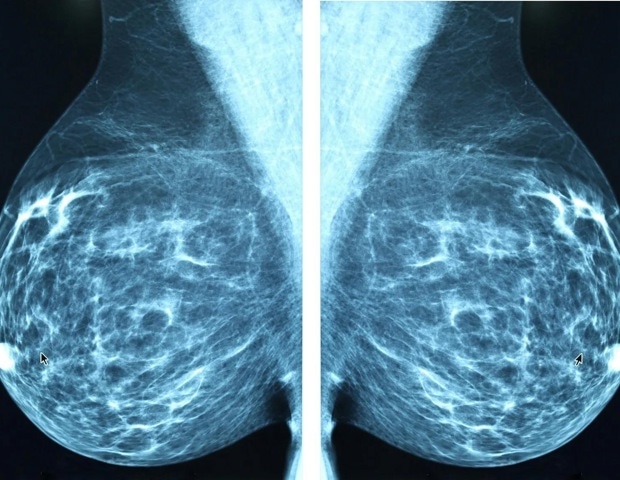

В международном исследовании, проведенном Калифорнийским университетом в Лос-Анджелесе, исследователи показали, что гиредестрант, пероральный селективный антагонист и деградатор эстрогеновых рецепторов нового поколения (SERD), при назначении в качестве адъювантной терапии на ранней стадии (1-3)-положительного по HER2-позитивному HER2-позитивному раку молочной железы, значительно снижает риск возвращения заболевания по сравнению со стандартной гормональной терапией, долгое время считавшейся основой Лечение.

Результаты указывают на потенциальный новый вариант лечения наиболее распространенного подтипа рака молочной железы, на который приходится примерно 70% всех случаев и чаще всего диагностируется на стадиях 1, 2 или 3.